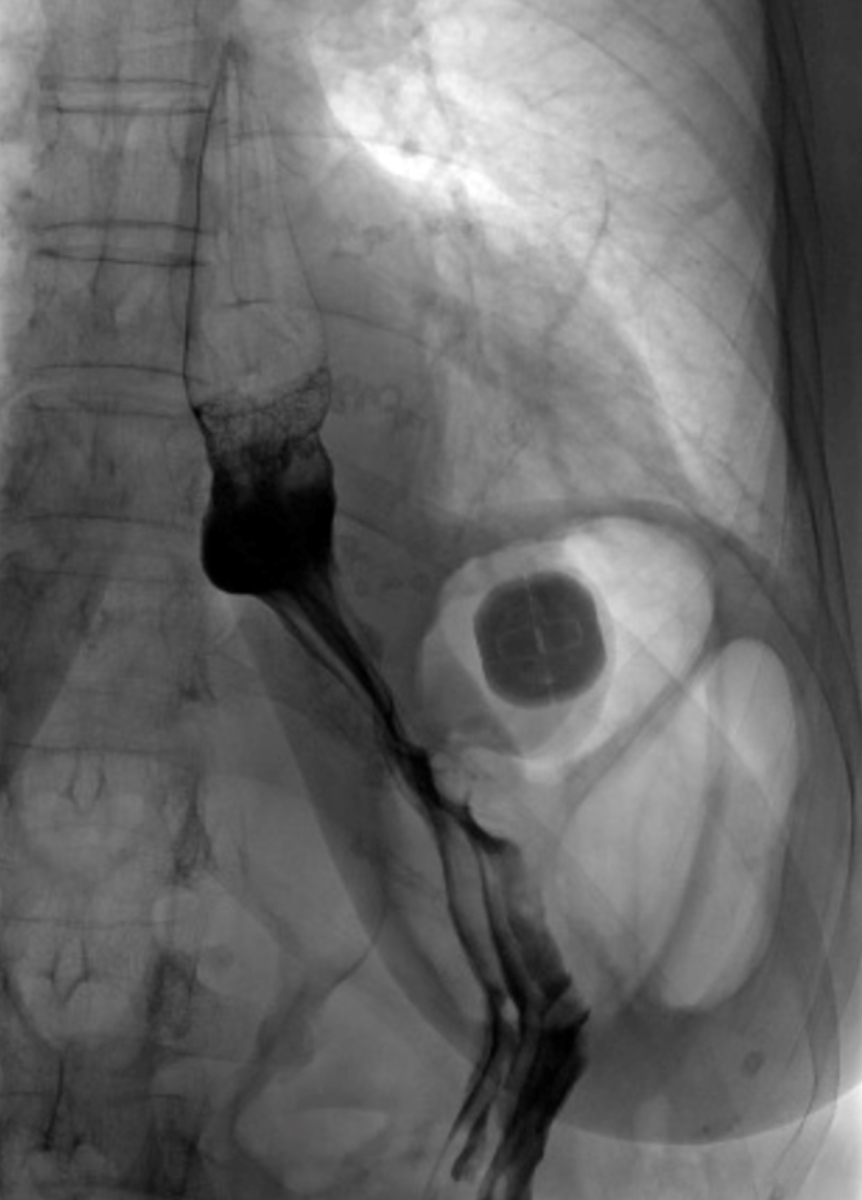

All patients underwent imaging (video fluoroscopy) on postoperative day one, and the correct positioning of the RefluxStop™ device was confirmed (figure 2). The patients’ median hospital stay was four days (IQR = 3–5 days). All patients tolerated the prescribed diet as described in the Methods section.

Figure 2Video oesophagram on postoperative day one depicting the correct positioning of the RefluxStop™ device, leaving the food passageway unaffected.